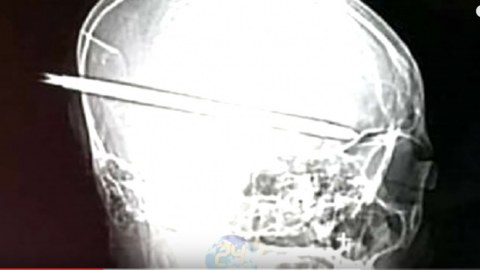

เผยภาพเอ็กซเรย์กะโหลก "น้องปอนด์" ไขควงทะลุถึงก้านสมอง